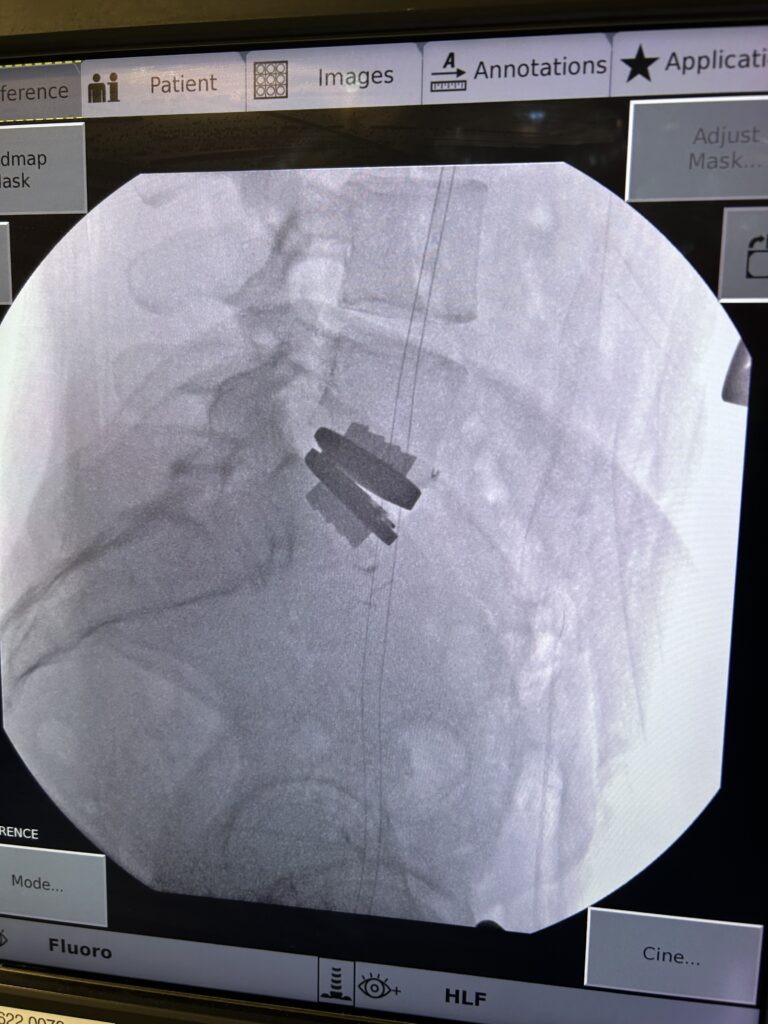

Dr. Daniel Choi recently performed a lumbar total disc replacement at St. Francis Hospital, reflecting an important professional milestone and the continued expansion of advanced spine surgery options on Long Island. Dr. Choi is one of few spine surgeons on Long Island offering lumbar disc replacement, a highly specialized procedure designed to preserve motion in the lower spine.

The procedure uses the prodisc® L Total Disc Replacement system from Centinel Spine, one of the most studied lumbar disc replacement technologies in the world. Backed by decades of clinical research, the prodisc® L system is designed to restore disc height, maintain motion, and accommodate a patient’s individual lumbar anatomy.